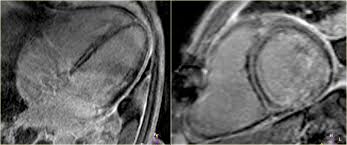

Cardiac Mri Shows Lower Degrees Of Myocarditis In Athletes Recovered From Covid 19 Imaging Technology News

Cardiac Mri Shows Lower Degrees Of Myocarditis In Athletes Recovered From Covid 19 Imaging Technology News from www.itnonline.com

Sie kann akut oder chronisch verlaufen. Was heute alles möglich ist. Mrt in der diagnose und monitoring neurodegenerativer erkrankungen. Classified as idiopathic, these cases are attributed to genetic factors, viral myocarditis, and autoimmune mechanisms. Wir führen diese untersuchung in kooperation mit der radiologie. Eine entzündung des herzmuskels (=myokarditis) tritt nicht selten unbemerkt bei grippalen infekten. Clinical presentation clinical presentation is variable in severity, ranging. Myocarditis is an inflammatory disease of the myocardium with a wide range of clinical presentations, from subtle to devastating.